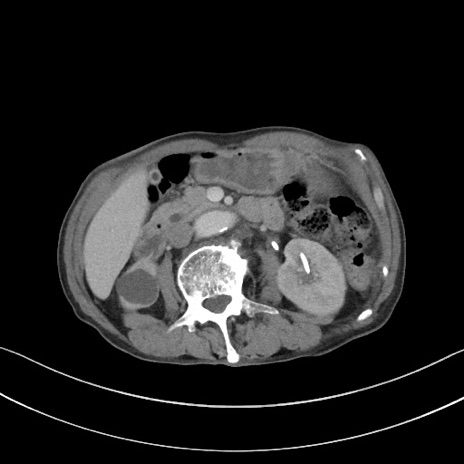

【症例】 70歳代男性

【主訴】右鼠径部腫瘤、疼痛

【現病歴】本日朝より上記主訴あり、受診。

【既往歴】膀胱癌にて膀胱全摘、両側尿管皮膚瘻

【データ】WBC 5600、CRP 0.56